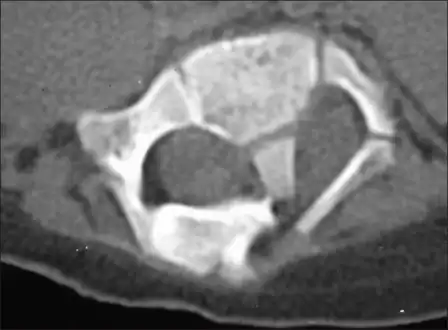

Diastematomyelia usually occurs between 9th thoracic and 1st sacral levels of the spinal column with most being at the level of the upper lumbar vertebra. Cervical diastematomyelia is a very rare entity. The extent (or length of spinal cord involved) varies from one affected individual to another. In approximately 60% of patients with diastematomyelia, the two hemicords, each covered by an intact layer of pia arachnoid, travel through a single subarachnoid space surrounded by a single dural sac. Each hemicord has its own anterior spinal artery. This form of diastematomyelia is not accompanied by any bony spur or fibrous band and is rarely symptomatic unless hydromyelia or tethering is present. The other 40% of patients have a bony spur or a fibrous band that passes through the two hemicords. In these cases, the dura and arachnoid are split into two separate dural and arachnoidal sacs, each surrounding the corresponding hemicord which are not necessarily symmetric. Each hemicord contains a central canal, one dorsal horn (giving rise to a dorsal nerve root), and one ventral horn (giving rise to a ventral nerve root.) One study showed the bony spur typically situated at the most inferior aspect of the dural cleft. They advised that if the imaging appears to show otherwise, a second spur (present in about 5% of patients with diastematomyelia) is likely to be present.

Adult presentation in diastematomyelia is unusual. With modern imaging techniques, various types of spinal dysraphism are being diagnosed in adults with increasing frequency. The commonest location of the lesion is at first to third lumbar vertebrae. Lumbosacral adult diastematomyelia is even rarer. Bony malformations and dysplasias are generally recognized on plain x-rays. MRI scanning is often the first choice of screening and diagnosis. MRI generally give adequate analysis of the spinal cord deformities although it has some limitations in giving detailed bone anatomy. Combined myelographic and post-myelographic CT scan is the most effective diagnostic tool in demonstrating the detailed bone, intradural and extradural pathological anatomy of the affected and adjacent spinal canal levels and of the bony spur.